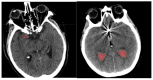

Objectives: Subarachnoid Hemorrhage (SAH) is a serious neurological emergency case with a higher mortality rate. An automatic SAH detection is needed to expedite and improve identification, aiding timely and efficient treatment pathways. The existence of noisy and dissimilar anatomical structures in NCCT images, limited availability of labeled SAH data, and ineffective training causes the issues of irrelevant features, overfitting, and vanishing gradient issues that make SAH detection a challenging task. Methods: In this work, the water waves dynamic factor and wandering strategy-based Sand Cat Swarm Optimization, namely DWSCSO, are proposed to ensure optimum feature selection while a Parametric Rectified Linear Unit with a Stacked Convolutional Neural Network, referred to as PRSCNN, is developed for classifying grades of SAH. The DWSCSO and PRSCNN surpass current practices in SAH detection by improving feature selection and classification accuracy. DWSCSO is proposed to ensure optimum feature selection, avoiding local optima issues with higher exploration capacity and avoiding the issue of overfitting in classification. Firstly, in this work, a modified region-growing method was employed on the patient Non-Contrast Computed Tomography (NCCT) images to segment the regions affected by SAH. From the segmented regions, the wide range of patterns and irregularities, fine-grained textures and details, and complex and abstract features were extracted from pre-trained models like GoogleNet, Visual Geometry Group (VGG)-16, and ResNet50. Next, the PRSCNN was developed for classifying grades of SAH which helped to avoid the vanishing gradient issue. Results: The DWSCSO-PRSCNN obtained a maximum accuracy of 99.48%, which is significant compared with other models. The DWSCSO-PRSCNN provides an improved accuracy of 99.62% in CT dataset compared with the DL-ICH and GoogLeNet + (GLCM and LBP), ResNet-50 + (GLCM and LBP), and AlexNet + (GLCM and LBP), which confirms that DWSCSO-PRSCNN effectively reduces false positives and false negatives. Conclusions: the complexity of DWSCSO-PRSCNN was acceptable in this research, for while simpler approaches appeared preferable, they failed to address problems like overfitting and vanishing gradients. Accordingly, the DWSCSO for optimized feature selection and PRSCNN for robust classification were essential for handling these challenges and enhancing the detection in different clinical settings.